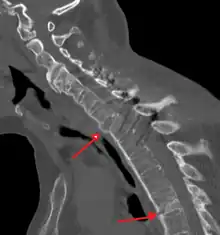

Fracture of the T5 and C7 vertebra due to trauma in a person with ankylosing spondylitis as seen on a CT scan

Prognosis is related to disease severity.[9] AS can range from mild to progressively debilitating and from medically controlled to refractory. Some cases may have times of active inflammation followed by times of remission resulting in minimal disability while others never have times of remission and have acute inflammation and pain, leading to significant disability.[9] As the disease progresses, it can cause the vertebrae and the lumbosacral joint to ossify, resulting in the fusion of the spine.[35] This places the spine in a vulnerable state because it becomes one bone, which causes it to lose its range of motion as well as putting it at risk for spinal fractures. This not only limits mobility but reduces the affected person's quality of life. Complete fusion of the spine can lead to a reduced range of motion and increased pain, as well as total joint destruction which could lead to a joint replacement.[36]

Osteoporosis is common in ankylosing spondylitis, both from chronic systemic inflammation and decreased mobility resulting from AS. Over a long-term period, osteopenia or osteoporosis of the AP spine may occur, causing eventual compression fractures and a back "hump".[37] Hyperkyphosis from ankylosing spondylitis can also lead to impairment in mobility and balance, as well as impaired peripheral vision, which increases the risk of falls which can cause fracture of already-fragile vertebrae.[37] Typical signs of progressed AS are the visible formation of syndesmophytes on X-rays and abnormal bone outgrowths similar to osteophytes affecting the spine. In compression fractures of the vertebrae, paresthesia is a complication due to the inflammation of the tissue surrounding nerves.